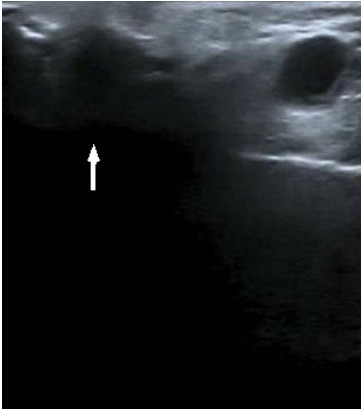

Se realizó punción-aspiración con aguja fina (PAAF) guiada con ecografía del lóbulo superficial de la parótida derecha (Figura 3), que fue positiva para malignidad, con informe anatomopatológico compatible con metástasis de carcinoma neuroendocrino de origen cutáneo.